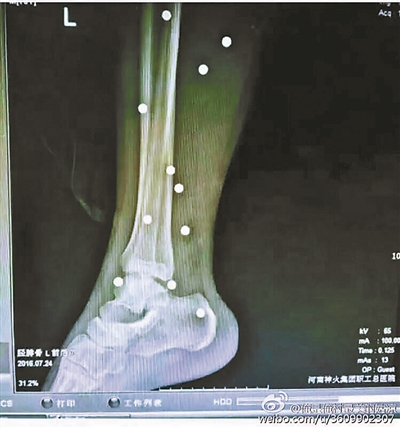

傷者體內(nèi)取出的鋼珠

爆炸導(dǎo)致鋼珠遍布傷者身體各處

黃明的伯伯對北青報記者表示,由于黃明直接踩到了爆炸物,所以傷情最為嚴重,“他的腿被炸斷,身體內(nèi)被炸進了40多顆鋼珠。手術(shù)后已經(jīng)從體內(nèi)取出29顆鋼珠,還有十多顆鋼珠沒有取出來?!备鶕?jù)黃明的入院記錄,他全身有多處爆炸傷,且全身多處異物存留。

爆炸發(fā)生時,陳浩的位置與黃明靠得很近,因此也受傷較重。他告訴北青報記者,經(jīng)過10多個小時的手術(shù)后,醫(yī)生從他身體里取出了12顆鋼珠。目前,他和黃明兩人經(jīng)過手術(shù)后,已從重癥監(jiān)護室轉(zhuǎn)至普通病房。其余三人中,陳剛的臀部受傷,當(dāng)天晚上在醫(yī)院清理完傷口后便回了家,而同行的兩名女生身上有一些擦傷。